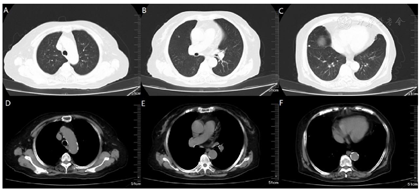

钙离子(我院2020年12月17日):3.91mmol/L。钙离子(我院2021年4月17日):3.5mmol/,多次复查钙离子明显升高。血气分析(2021年4月22日未吸氧):PH 7.48,PaCO2 37mmHg,PaO2 58mmHg,HCO3-:27.6mmol/L,BE 4.1mmol/L,Lac 1.6mmol/L,K+ 4.1mmol/L,THbc 84g/L。骨代谢六项:降钙素3.87pg/ml,甲状旁腺素46.00pg/mL,β-胶原降解产物2.480ng/mL,总I型胶原氨基端延长肽315.000ng/mL,骨钙素47.700ng/mL,25羟维生素D 4.700ng/ml;甲功八项:甲状腺过氧化物酶抗体(ATPO) 10.80U/ml,甲状腺球蛋白抗体(ATG)>4000U/mL,甲状腺球蛋白(TG) 0.20ng/ml,三碘甲腺原氨酸(TT3) 1.30nmol/L,甲状腺素(TT4) 46.80nmol/L,游离T3(FT3) 2.48pmol/L,游离T4(FT4) 6.69pmol/L,高灵敏促甲状腺素(TSH) 9.470mIu/L;肿瘤标志物全套(女):肿瘤相关抗原125(CA125) 52.70U/ml,肿瘤相关抗原153(CA15-3) 31.90U/ml,细胞角蛋白19片段(Cyfra211) 2.78ng/ml,异常凝血酶原(PIVKA-Ⅱ) 32.700mAU/ml,β2-微球蛋白(β2-MG) 3.04μg/mL,人绒毛膜促性腺激素(HCG) 7.54mlU/ml,绝经前ROMA值(Pre-ROMA) 97.19%,绝经后ROMA值(Post-ROMA) 81.68%,胃泌素释放肽前体(ProGRP) 279.0pg/ml。胸部平扫CT(我院2020年12月18日图1):右肺中叶及左肺下叶结节,右肺钙化灶。气管及主支气管管壁钙化。胸部平扫CT(我院,2021年4月19日图2):两肺见弥漫性、松散性沿支气管及血管分布的结节状及团片状高密度影,以两肺上叶为著,呈对称性改变,纵隔窗大部分病灶已实变,CT值约为100HU。胸部增强CT(我院,2021年4月25日):两肺见弥漫性、松散性沿支气管及血管分布的团絮状、棉花团样密度增高影及磨玻璃密度影,以两肺上叶为著,呈对称性改变,纵隔窗大部分病灶已实变,CT值约为100HU,增强扫描动脉期CT值约127HU,静脉期CT值约111HU。诊断提示:两肺代谢性疾病,考虑转移性肺钙化。PET/CT提示双肺改变考虑非肿瘤性病变,不除外肺泡蛋白沉积症可能,建议相关检查。电子支气管镜检查,镜下未见明显异常(图3),肺泡灌洗液色清亮。右肺上叶灌洗液送检脱落细胞回报示标本内见噬细胞、偶见上皮细胞,未见到恶性细胞。灌洗液病原微生物宏基因检测回报示白色念珠菌(序列数:4091)、光滑念珠菌(序列数:726)、EB病毒(序列数:33)。2021年5月11日行CT引导下经皮肺穿刺活检(图4),于右肺上叶穿刺获得2条约2.3cm长暗红色肺组织,送检肺组织常规病理及病原微生物宏基因检测。病理回报示(右肺上叶)肺泡结构破坏,肺间质纤维母细胞增生,有淋巴细胞、浆细胞浸润,其内见网络样钙化,局部见有机化及玻璃样变,并见有增生的肺泡上皮,细胞有异型,胞浆嗜酸,考虑为反应性增生,病变形态不能除外转移性钙化引起的弥漫性肺泡损伤性病变,请结合临床(图5)。肺组织病原微生物宏基因检测回报示白色念珠菌(序列数:1)、EB病毒(序列数:1)。全身骨显像示双肺弥漫性高密度伴放射性浓聚,考虑转移性钙化,结合临床资料,首先考虑肺泡微石症,肿瘤性疾病待排。甲状旁腺显像未见明显异常。

本病例存在以下两个特点:1.肺部影像学表现重,双肺多发高密度影,沿支气管及血管分布,以两肺上叶为著,小叶中心分布为主,部分存在实变。具有且弥漫性、对称性的特点。2.对比2020年12月17日及2021年4月19日两次胸部平扫CT,可见肺部影像学快速进展,但咳嗽、咳痰及活动后呼吸困难症状较前未见明显加重。入院后高度怀疑原发肺癌或转移性肺癌,考虑到患者81岁,心肺功能差,建议患者完善PET/CT密切病变性质,结果回报示双肺改变考虑非肿瘤性病变,不除外肺泡蛋白沉积症可能。胸部增强CT及全身骨扫描考虑转移性肺钙化。笔者认为病理是诊断转移性肺钙化的金标准,遂利用呼吸介入手段尽早行肺活检。患者81岁,存在I型呼吸衰竭,心功能欠佳,对气管镜操作医生要求极高。我中心呼吸内镜医生完成气管镜常规检查及肺泡灌洗后,患者出现血氧降低,未能通过气管镜获得肺活检标本。气管镜灌洗液病原微生物高通量测序提示白色念珠菌、光滑念珠菌、EB病毒感染,但不考虑引发此影像学改变。后续通过CT引导下经皮肺穿刺活检获得病理,病理结果不除外转移性钙化。综合患者病史,胸部增强CT、全身骨显像及病理结果,可明确诊断为转移性肺钙化,但病因尚不明确。患者无透析、器官移植病史,甲状旁腺功能及甲状旁腺显像未见明显异常,可除外原发性或继发性甲状旁腺功能亢进。患者既往因肌酐升高,4个月前于我院诊断为慢性肾脏病,但本次入院多次复查肾功能均为正常。根据骨代谢六项结果,及血钙、血磷趋势,不支持为慢性肾脏病所致转移性钙化。因患者年龄较大,给予降低血钙后,血钙维持在正常范围内,症状较前缓解,建议患者出院观察,定期复查胸部CT及钙离子。